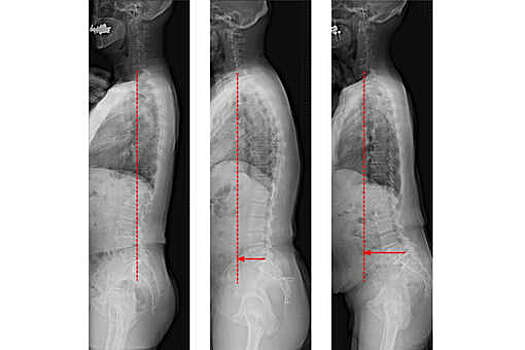

Ученые из Университета Шиншу показали, что нарушения осанки могут быть связаны с риском возникновения когнитивных расстройств у пожилых. Результаты представлены в Scientific Reports. Исследователи проанализировали данные пожилых (от 50 до 89 лет) японцев из города Обусе, Нагано. Они обнаружили, что у пожилых японцев со смещенной саггитальной вертикальной осью (SVA) был выше риск легких когнитивных нарушений. SVA представляет собой прямую линию, опущенную из тела позвонка С7 перпендикулярно полу. В норме она должна заканчиваться в крестце, но с возрастом может смещаться вперед. Для женщин с отклонением SVA ≥ 70 мм снижение когнитивных функций наблюдалось в любом возрасте. Для мужчин — при отклонении более 100 мм в любом возрасте, а также при отклонении SVA ≥ 90 мм, начиная с 70 лет и отклонении SVA ≥ 70 мм — с 80 лет. Легкие когнитивные нарушения определяются как когнитивные жалобы со стороны человека или других лиц, но они еще не считаются деменцией. В районах, где дорогостоящее оборудование для диагностики или дополнительное время для медицинского тестирования ограничены, важно иметь простые способы выявления пациентов с высоким риском таких нарушений. Практикующие врачи, участвовавшие в исследовании, подчеркнули, что в своей практике часто видят, что пожилые люди могут уменьшить проявления деменции или даже остановить ее прогрессирование с помощью физических упражнений.